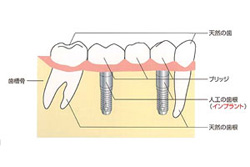

インプラントとは

第3の治療の選択肢のインプラントとは、どのような治療なのか?

図のように(右:天然歯/左:インプラント)、歯の根に代る人工的な根を骨の中に埋め込んだ上で、その上に歯を形成しようと考えたのがインプラントです。

実際は骨に穴をあけて、そこにチタンなどの人工歯根を埋め込み、それが骨とがっちりと結合した状態で、その上に人工の歯を取りつける治療方法です。